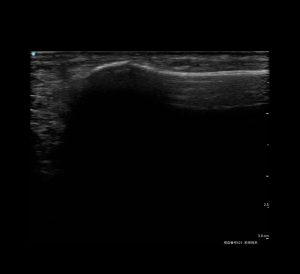

【下駄骨折が起こる位置】

見た目や痛みだけでは判断できないため、早期の画像検査が重要です。